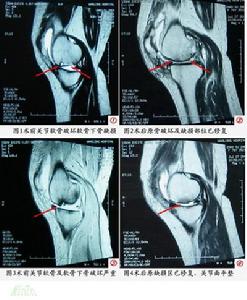

五、影像學檢查

關節疾患X線拍片是常規的檢查方法之一主要查看骨質的變化,特別是對關節部位骨腫瘤,骨質破壞畸形、關節滲液腫脹,有明顯的診斷意義CT及MRI也是檢查關節病變新的方法,除對骨質顯像之外,對關節內的軟骨軟組織結構能夠顯像丶,對診斷半月板損傷有其先進之處,這是普通X線拍片所不能比擬的其缺點是價格較昂貴。

1)半月板損傷:多有外傷史關節間隙可有壓痛點,休息後疼痛消失,MeMurray征陽性,可有關節交鎖。

3)軟骨損傷:關節軟骨損傷後可發生骨折或軟骨

5)臏骨軟骨軟化症:青壯年易發生膝前疼痛人坐後站立疼痛上、下樓梯疼痛,壓股試驗陽性